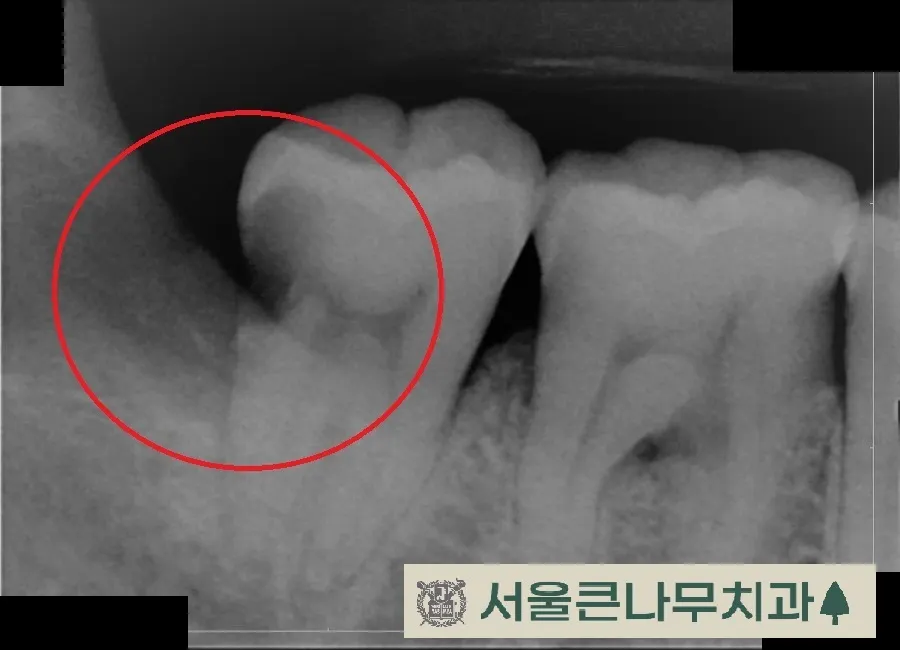

두번째로 치아 사이에 생긴 충치입니다.

빨간색 화살표 사이 보이는 부분이 썩어있는 부분입니다.이렇게 비스듬하게 자리잡고 있는 사랑니의 경우 치아 사이에 고인 찌꺼기들에 의해 앞 치아까지 영향을 주어 충치가 진행되는데요.

보이는 것과 같이 사이충치가 진행되어 앞치아까지 영향을 준 모습입니다.